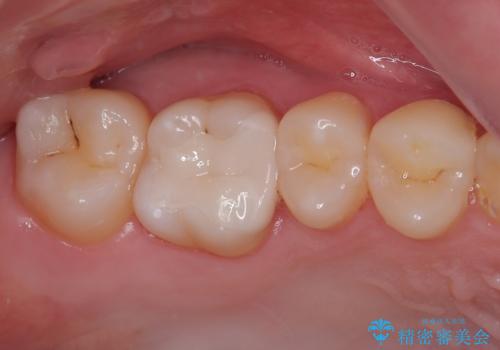

銀歯を気にせずに笑うことができると満足していただきました。